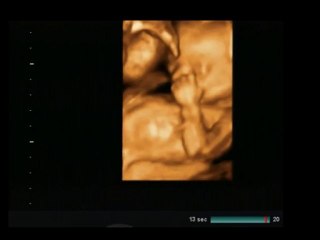

Uploaded: 2011-04-22

Duration: 00:40